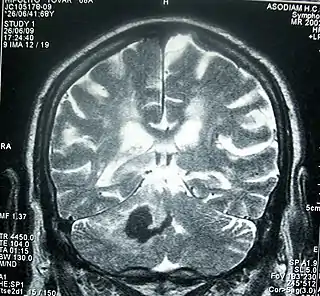

![]() RMN de cráneo que muestra una hemorragia intracerebral profunda (cerebelo): zona oscura, 30 horas desde el inicio de la enfermedad actual. | ||